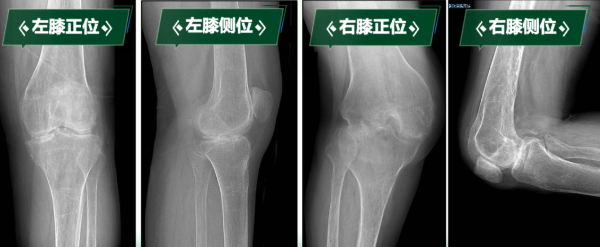

“真不敢相信,我能站起來,還能走路……”劉阿姨因罹患類風濕性關節炎多年,骨質受到嚴重侵蝕,導致雙膝關節逐漸纖維性強直,更加棘手的是,雙膝強直于兩個極端體位,左膝關節無法彎曲,像“木棍”一樣始終處于伸直狀態;右膝長